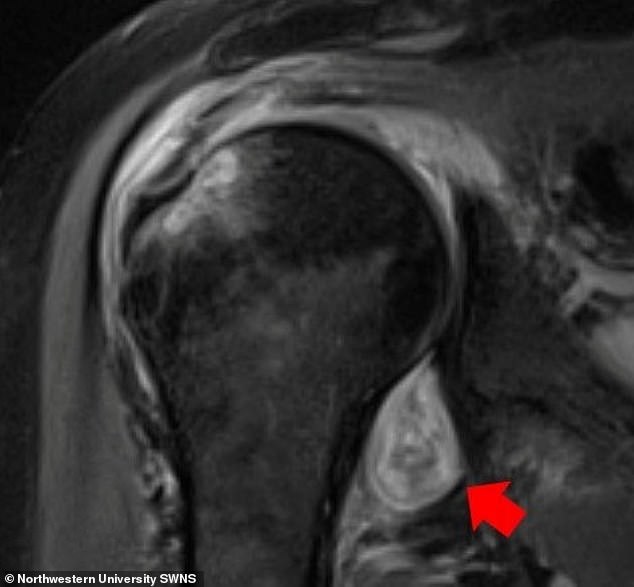

Trong nghiên cứu mới thực hiện bởi các nhà khoa học từ Đại học Northwestern (Mỹ), các nhà nghiên cứu phát hiện ra COVID-19 có thể gây ra các vấn đề về cơ và khớp lâu dài, bao gồm viêm khớp, hoại thư và 'ngón chân COVID’.

Ảnh chụp y khoa của các bệnh nhân gặp phải các triệu chứng này cho thấy COVID-19 có thể khiến hệ miễn dịch của cơ thể tự tấn công chính nó, dẫn đến các vấn đề thấp khớp kéo dài.

Các nghiên cứu trước đây cũng tìm ra mối liên hệ giữa nhiễm virus corona và đau cơ hoặc khớp, nhưng đây là lần đầu tiên các triệu chứng này được minh họa qua hình ảnh y khoa.

Trong nghiên cứu của Đại học Northwestern, các nhà khoa học sử dụng các kỹ thuật hình ảnh khác nhau bao gồm chụp CT, MRI và siêu âm, để hình dung nguyên nhân gây hoại thư và các cơn đau cơ và khớp lâu dài ở bệnh nhân COVID-19.

COVID-19 gây ra bệnh viêm khớp dạng thấp ở bệnh nhân này với triệu chứng đau vai kéo dài sau khi các triệu chứng COVID khác đã hết.